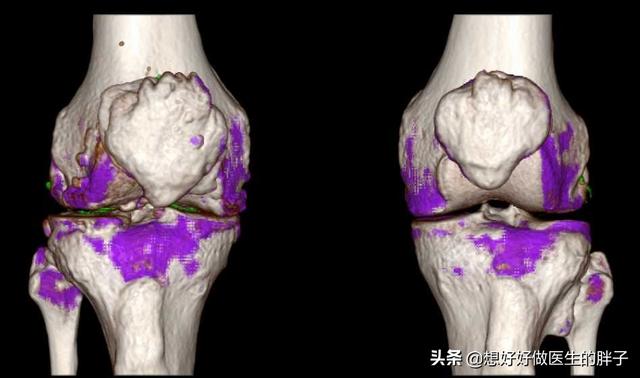

S'il vous plaît, nous devons croire en la science.Que l'on veuille ou non aller à l'hôpital, l'hôpital est là.Si vous pensez être atteint de goutte, rendez-vous à l'hôpital pour un examen professionnel.Réaliser un scanner à double énergie, un test sanguin d'acide urique ou une échographie.Cela vous aidera à identifier s'il y a des dépôts de cristaux d'urate dans certaines parties du corps et à déterminer s'il y a un risque de crise de goutte.Ne vous faites jamais aveuglément une opinion et ne vous traitez pas vous-même à la maison, ce qui entraînerait des retards dans l'évolution de votre état.。

La deuxième étape consiste à effectuer une étude d'imagerie, par exemple pour détecter un "signe de double piste" sur l'échographie ou pour effectuer un "signe de double piste" sur l'échographie.La tomodensitométrie à double énergie révèle des dépôts d'urateetc., puis ouLes radiographies révèlent un gonflement des tissus mous, une destruction des bords du cartilage et une irrégularité des surfaces articulaires.!

La goutte peut être détectée par imagerie, la présence de cartilage articulaire "signe de double piste", l'épanchement articulaire, l'érosion osseuse, etc., peuvent également être diagnostiqués par des indicateurs de la fonction rénale.